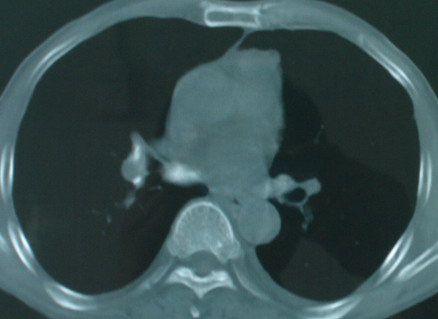

以下是引用医影拾贝在2008-6-3 18:48:00的发言:[br]双上肺弥漫性小结节影,纵隔窗内钙化淋巴结影,考虑血播性tb可能性较大,不除外肺ca可能

以下是引用卜一在2008-6-3 19:33:00的发言:[br]双肺结节,以双上肺分布为多,期间搀杂片状致密影及索条致密影。考虑:继发性肺结核伴血型播散可能性大。不除外肺泡ca的可能!另:椎体退变!

以下是引用panyishengct在2008-6-3 21:09:00的发言:[br]双上肺弥漫性小结节影,纵隔窗内钙化淋巴结影,考虑矽肺或/和tb可能性较大,不除外肺ca可能。腰椎考虑退变。 [br][br]